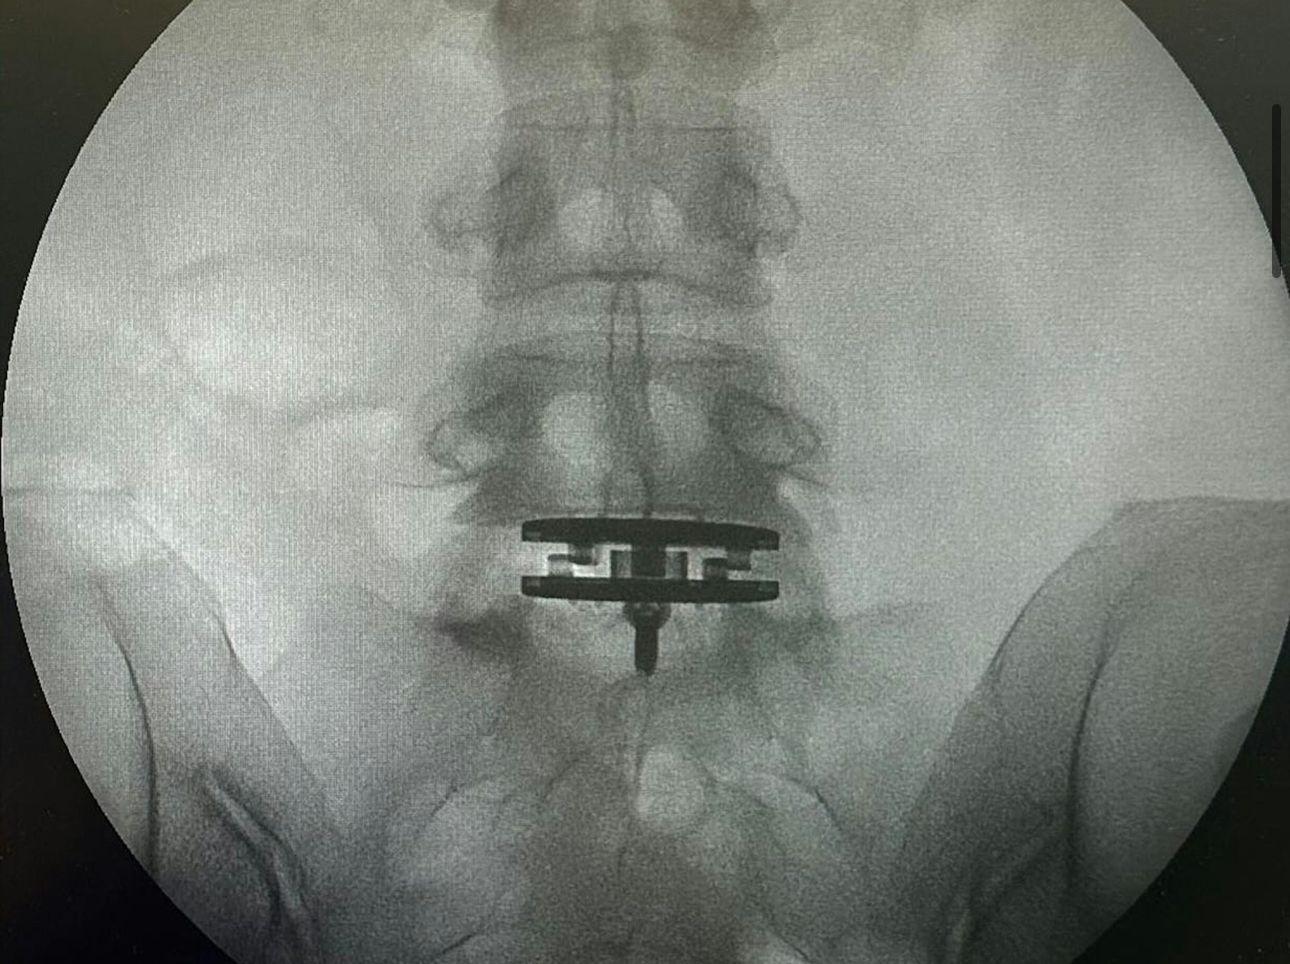

現年50歲的徐濠縈,在IG上載了數張X光片,可以見到片中腰椎接近盆骨的位置有東西矯正脊椎,她亦寫:「I have been suffering from back pain for many years due to a slipped disc issue in my lumbar spine.」透露腰椎間盤突出問題多年,一直飽受腰痛煎熬,嚴重影響了日常生活,熱愛運動的徐濠縈也被迫暫停,即使是打噴嚏的小動作,也會引起劇烈的疼痛,尤其這兩年過得特別難捱。事實上,徐濠縈於2022年已動過一次手術,可惜沒有好轉,她在醫生的建議下決定再次接受椎間盤手術,希望透過這次手術有所改善,她在自言這可能是她人生中繼20年前生下女兒後,最重要的一次手術。目前,徐濠縈已完成手術,正在家中休養。